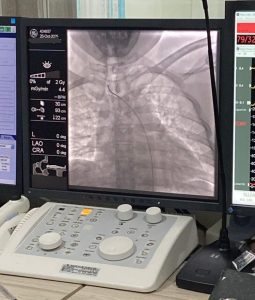

Kaltaraa1. Com, TARAKAN – Tindakan Digital Subtraction Angiography (DSA) kini membuka peluang besar bagi dunia medis di Kalimantan Utara untuk mendiagnosa berbagai penyakit pembuluh darah